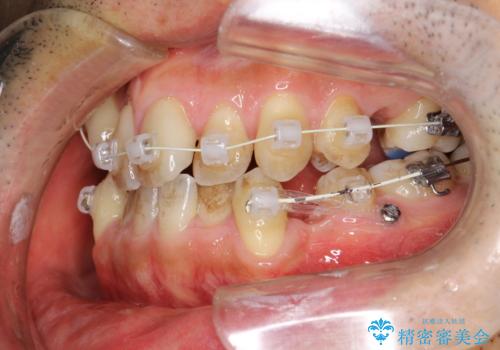

途中までは下顎は全体にワイヤーをはらずに、セクショナルワイヤーにて治療を進めています。

上顎は最初から全体にワイヤーをはっていましたが、上顎前歯部の歯肉退縮のリスクが高そうだったために、途中まで下顎と同じくセクショナルワイヤーで進めています。

患者様にはかなり満足していただける結果となりました。

八重歯(3番)などは歯肉移植も検討できればよいかなと思います。